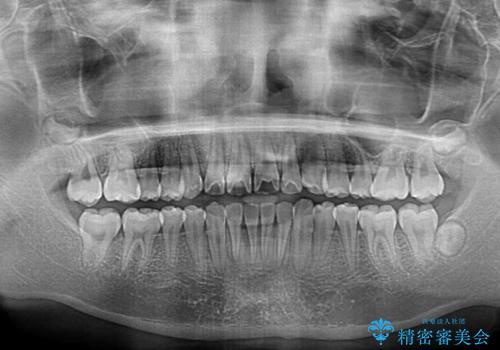

- 上下前歯のデコボコを改善したいとのことで来院された患者様です。

中学生と言うこともあり、1年強の短期間で終了しました。

歯磨きがしっかりとできないと虫歯になるリスクがありましたが、治療期間中は清潔な状態を保っていただけました。